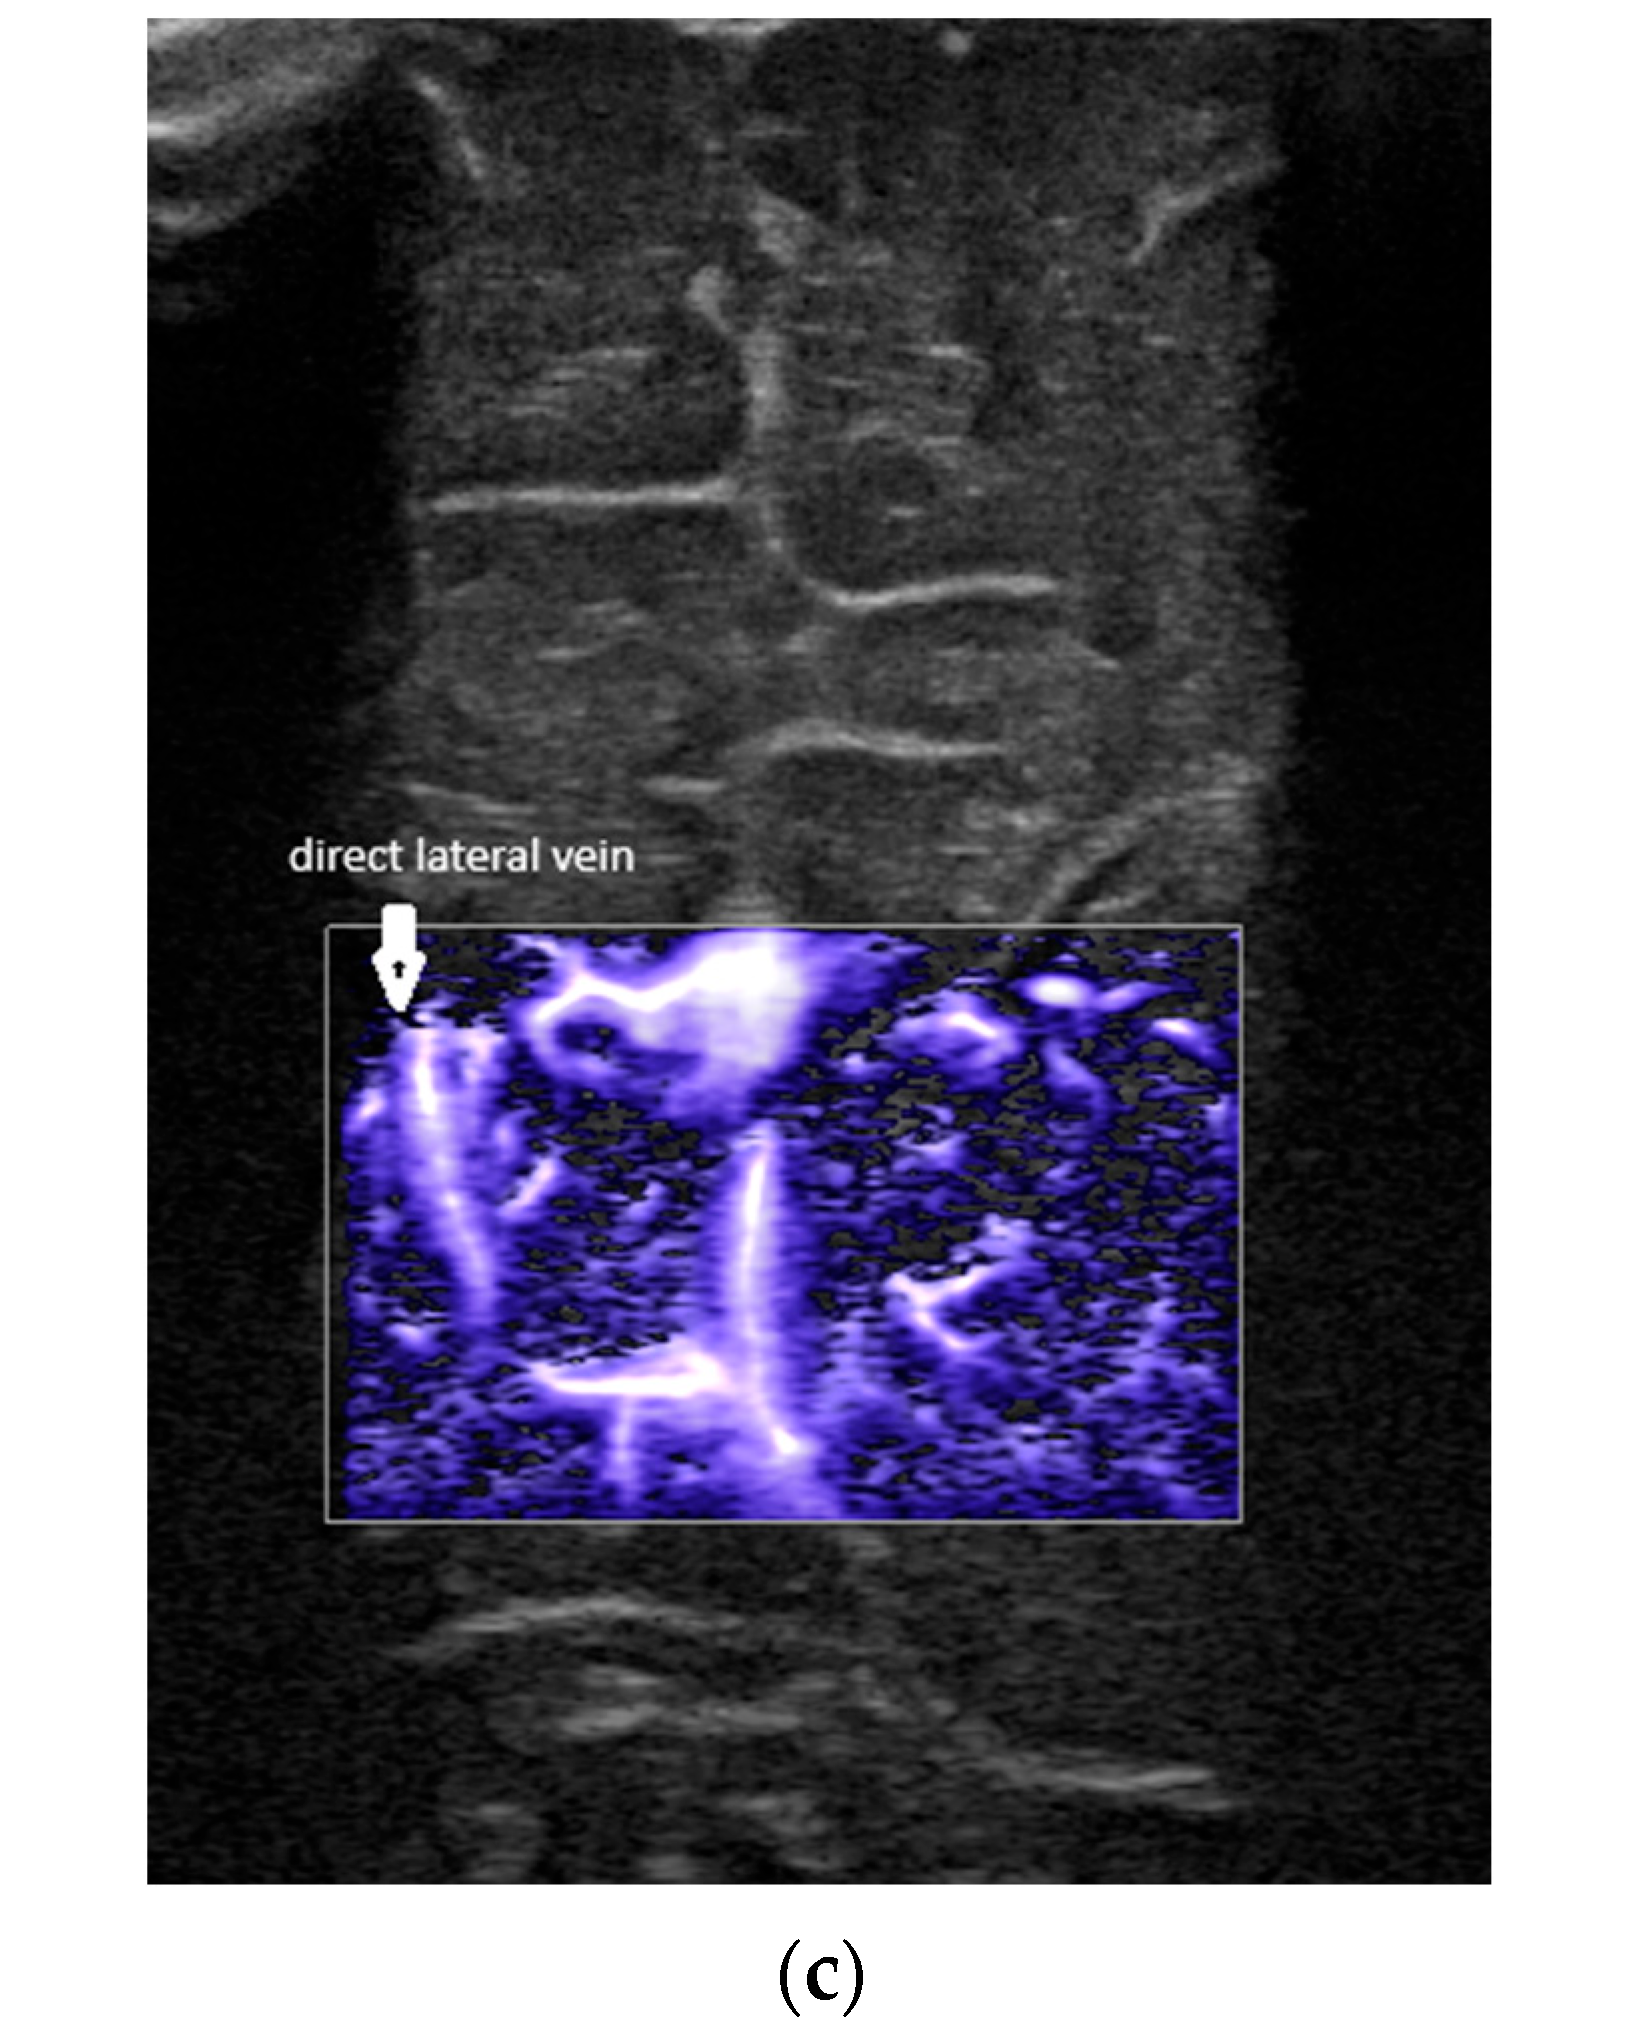

- A lack of identification of the confluence—wherein the terminal vein was absent on one or both sides—an example is the case presented in Figure 3, where the terminal vein was most probably draining in a direct lateral vein on the left side.